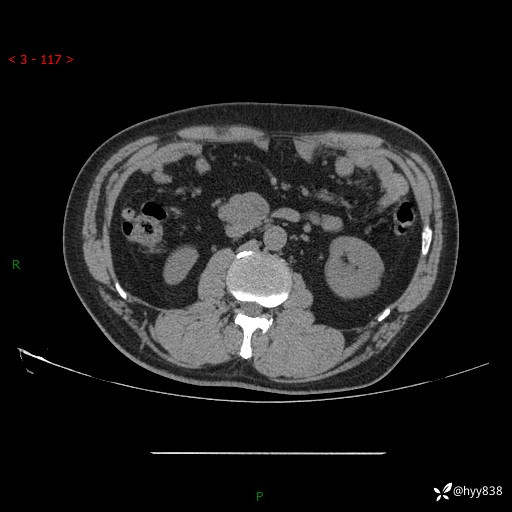

增强